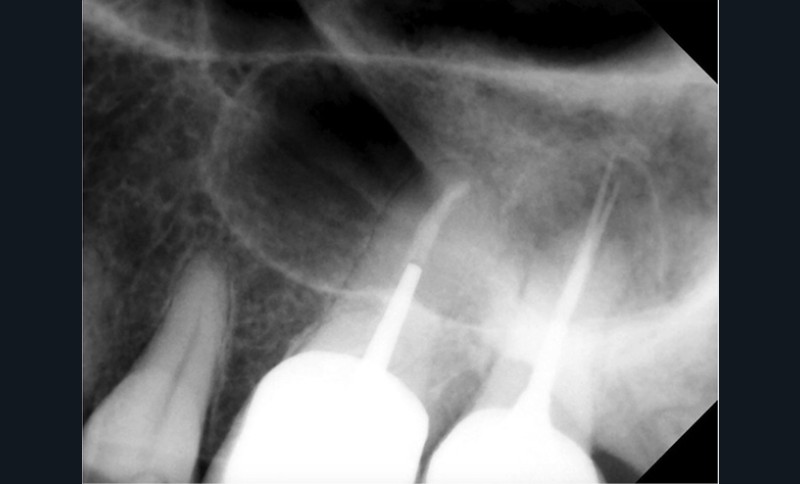

Si l’étude de Peters [18] nous montre que l’instrumentation laisse 35 % du volume canalaire non instrumenté, Ricucci et Siqueira montrent que la préparation physico-chimique n’élimine que partiellement les tissus nécrotiques à l’entrée des canaux latéraux, des isthmes et des ramifications apicales, en laissant des tissus enflammés et infectés, en association avec des lésions apicales [29] (fig. 4 et 5).

Fig. 4 – Coupe d’une racine mésiale de molaire mandibulaire avec deux canaux traités. Coupe à 3 mm de l’apex, coloration Brown et Brenn, technique modifiée par Taylor. Ces images montrent un isthme étroit avec une infection bactérienne, ce qui prouve l’importance de désinfecter et d’inclure l’isthme dans les traitements conventionnels et dans les rétropréparations apicales en chirurgie endodontique.

Si les isthmes sont particulièrement mis en évidence au niveau des molaires mandibulaires, cela devient médicalement important au niveau des molaires maxillaires.

La diffusion bactérienne et de leurs toxines, au niveau des molaires maxillaires est à l’origine d’un grand nombre de sinusites maxillaires chroniques, d’origine dentaire. Celles-ci sont principalement causées par l’absence de traitement du deuxième canal MV, qui existe dans 90 % des cas, et il est à noter que ces deux canaux – MV1 et MV2 – sont également reliés par un isthme.

Le nettoyage des isthmes intercanalaires reste un réel problème, et semble responsable de nombreux échecs [43]. Par ailleurs, il est nécessaire d’utiliser des instruments qui évitent de propulser les débris, tant apicalement que latéralement, en obturant les entrées isthmiques avec des débris compactés.

Le passage du laser est répété plusieurs fois, en début, au milieu et en fin de préparation. Un protocole peut alors être proposé : 40 mJ ; 20 Hz (fig. 7). L’utilisation de biocéramiques Bioroot (Septodont) ou Total Fill R (FKG) permet de sceller le système ainsi nettoyé, en assurant une action biologique de longue durée [46] (fig. 8a à c).